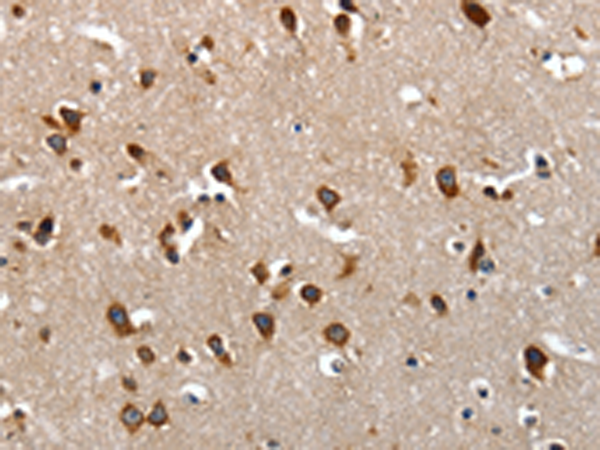

分类: 科研抗体货号: P11016别名:应用: IHC反应种属: Human, Mouse